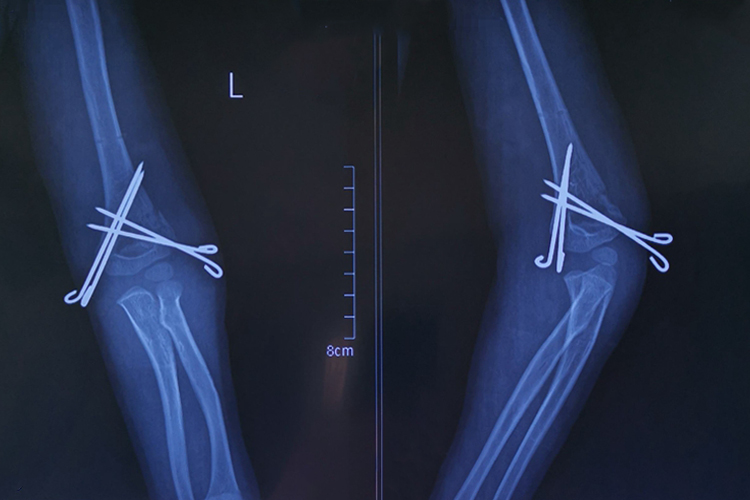

骨折示意图

肱骨髁上骨折可分为伸直型、屈曲型,具体如下:

伸直型:伸直型肱骨髁上骨折的特点是骨折线位于肱骨下端鹰嘴窝水平处或其上方,骨折的方向为前下至后上,骨折向前成角,远折端向后移位。

屈曲型:屈曲型肱骨髁上骨折的骨折线可为横断,骨折向后成角,远折端向前移位或无明显移位。